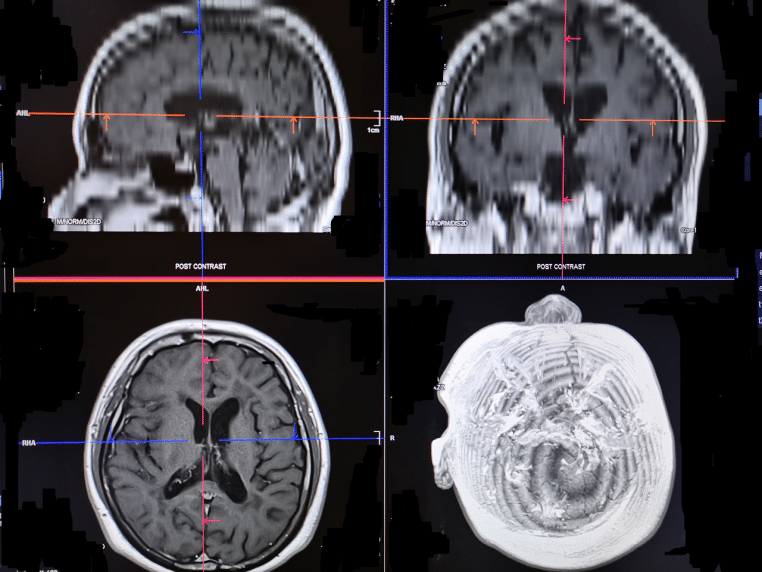

La communauté scientifique a déjà documenté des phénomènes cérébraux lors des tout derniers instants — jusqu’à des enregistrements d’activité en temps réel. L’olfaction pourrait être une clé supplémentaire, complémentaire des marqueurs cardiaques, respiratoires ou électriques. Pour l’instant, la littérature évoque surtout des hypothèses et des observations pilotes. L’étape suivante : standardiser les mesures, caractériser les profils de polyamines, corréler les courbes de concentration à l’état clinique et à l’EEG.